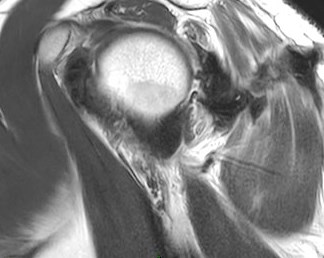

Figure 2 for case Stab wound

Figure 2

Discussion

Filled with hemorrhage. The infraspinatus took the brunt.